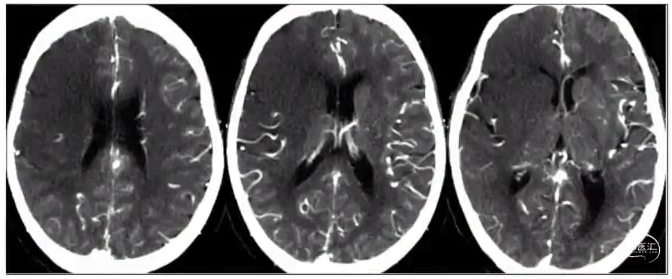

梗死灶评估——CT平扫(NECT)

急性缺血性卒中CT早期征象

豆状核模糊征

大脑中动脉高密度征

岛带征

脑实质低密度、灰白质界限消失、脑回肿胀、脑沟变浅

注:CT早期征象常提示不可逆梗死核心